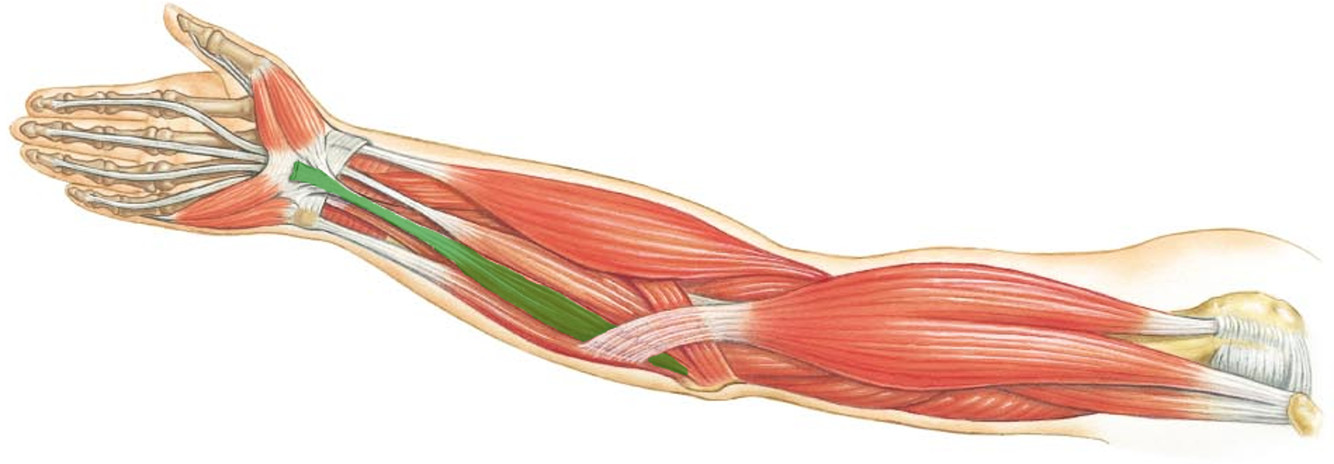

What is the innervation of this muscle?

Muscle - Pronator teres

Median nerve

What is the innervation of this muscle?

Muscle - Popliteus

Tibial nerve